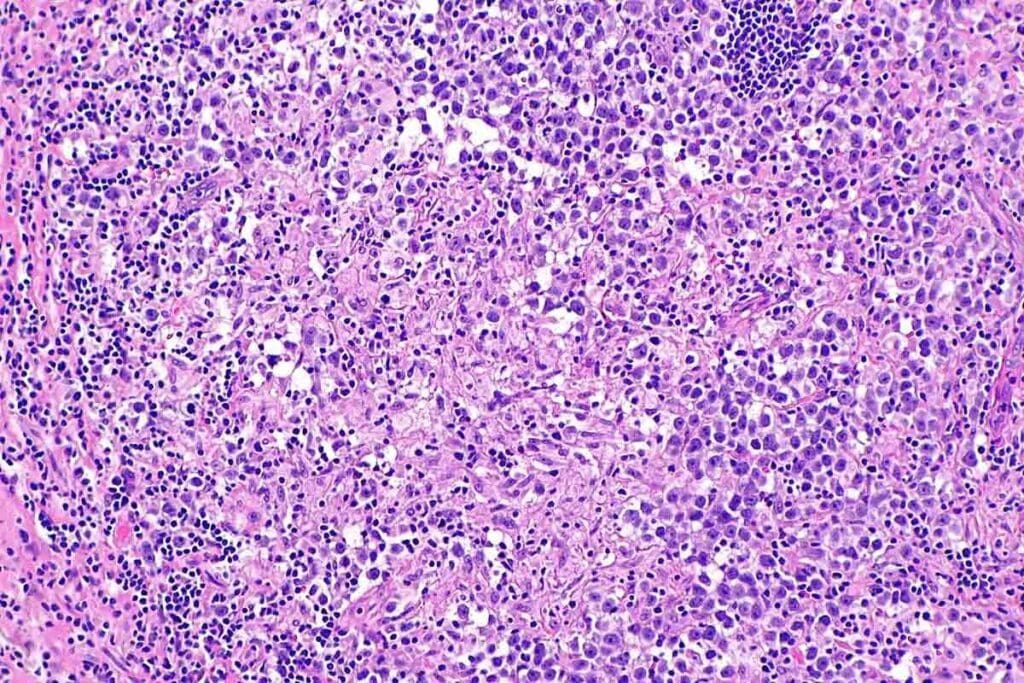

Bone Marrow Biopsy Findings

A bone marrow biopsy is key to diagnosing aplastic anemia. It looks at bone marrow tissue to see cell numbers and find any problems.

In aplastic anemia, the bone marrow has fewer cells. This is important to tell it apart from other pauses.

Histological Features of Aplastic Anemia

The bone marrow in aplastic anemia looks different. It has fewer cells and more fat cells. There’s no sign of cancer or fibrosis.

These signs help confirm aplastic anemia and rule out other bone marrow issues.